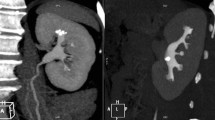

Surgeons must consider the optimal treatment strategy before performing PCNL, including the surgical positions and percutaneous access points. Surgical positions commonly used in PCNL include the prone and oblique positions. However, discussions regarding which position is more suitable for PCNL are ongoing [44, 45]. The difficulty of percutaneous renal access also varies according to position. As the lower kidney may be displaced medially and ventrally in the oblique position owing to gravity [46], even if punctured from the same point, the pass-through line will be different for each surgical position (Fig. 5).

Ultrasound image in the prone (a) and oblique (b) positions; the white dotted arrow indicates the puncture line to the target calyx. In the prone position, the puncture line passes through the cyst (a); on the other hand, it passes through near the cyst and reaches the target calix in the oblique position (b)

The success of PCNL depends on the proper choice of renal calyceal approach. Direct access to the calyx, where most of the calculi are located, is considered ideal. However, visceral organs, including the enlarged liver, spleen, and retrorenal colon, may interfere with the puncture. The superior calyceal approach is anatomically ideal for treating staghorn calculi because of its easy accessibility to many calyces [47, 48]. However, thoracic complications are more common with superior calyceal puncture. Munver et al. [47] reported that the risk of thoracic complications with supra-11th-rib puncture (23.1%) was 16 times higher than with supra-12th-rib puncture (1.4%). Preoperative check-ups using US in a position similar to that used during surgery may be required to prevent visceral and thoracic injuries.